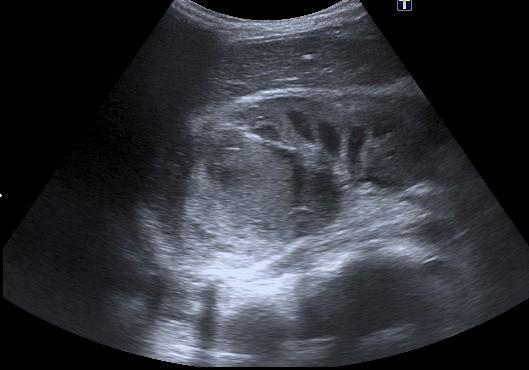

Ecografía:

- Masa renal bien definida e hiperecogénica de debido a la posible presencia de hemorragia, grasa, necrosis y raramente calcios.

- Las calcificaciones son raras. Su morfología es curvilínea (a diferencia del neuroblastoma = puntiforme).

- En ocasiones es posible diferenciar una pseudocapsula correspondiente a tejido renal sano comprimido.